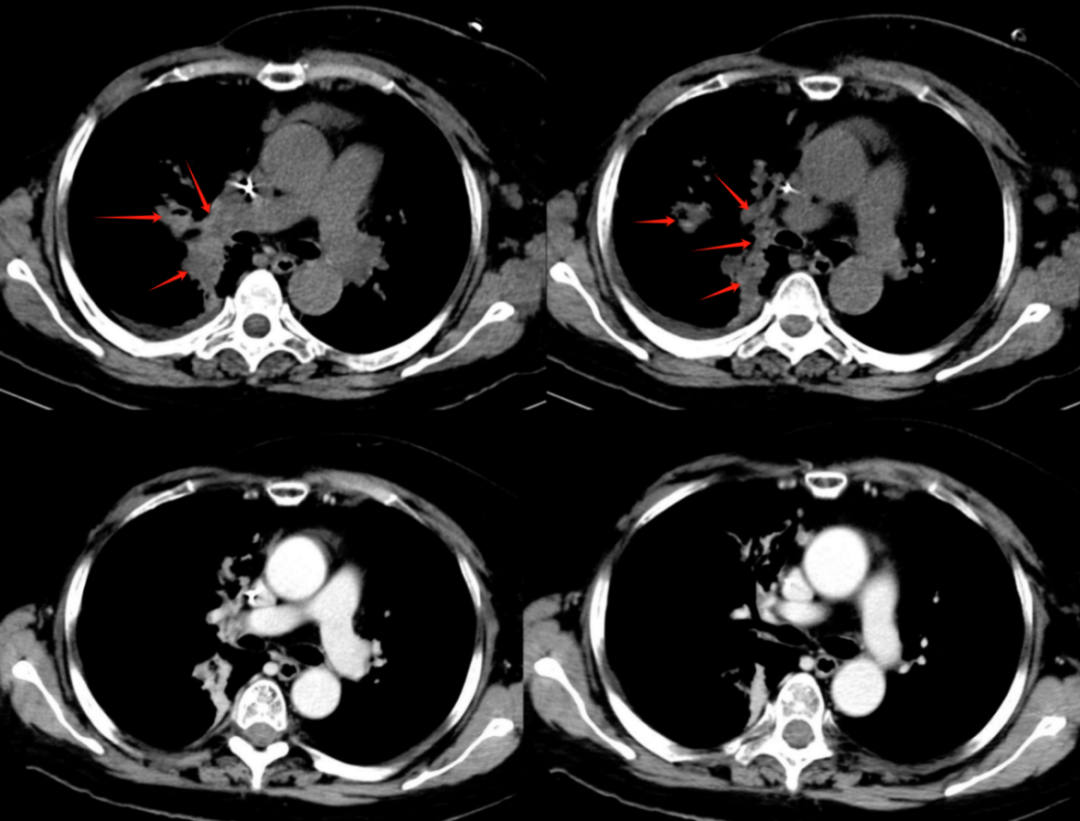

【學科風采】乳腺癌患者千里求醫(yī),成功治療多發(fā)腦轉移瘤、脊髓轉移、腦膜轉移、椎管內多發(fā)轉移結節(jié)、肺炎及肺門轉移患者